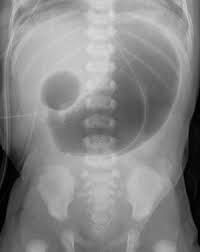

Duodenal atresia is a condition that some babies are born with (congenital disorder). Babies with duodenal atresia have a closure in the first part of their small intestines (duodenum). The closure causes a mechanical blockage that prevents the passage of milk and digestive fluids.